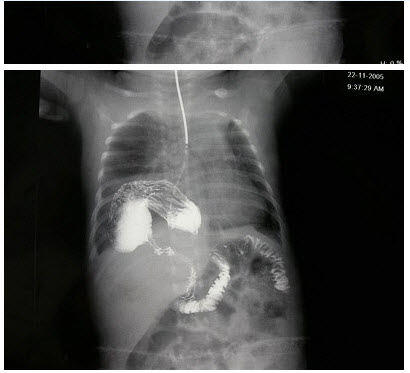

男,1岁零8个月,生长发育差,易患呼吸道感染,心悸气促,心脏正、侧位片检查如图所示,正确的描述和诊断是()

A.正位示心影向两侧扩大,心尖左移

B.肺纹理增多

C.侧位示心前间隙变窄,心后食管前三角间隙消失

D.房间隔缺损

E.室间隔缺损